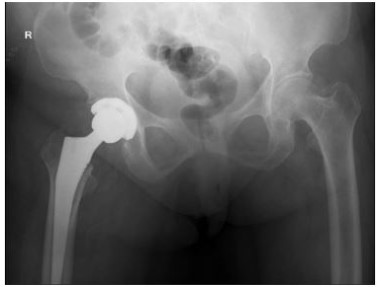

A female, aged 55, with 153 cm in height, 85 kg in weight and 36.3 in BMI. She was admitted to hospital on July 24, 2021 due to severe osteoarthritis of the right knee. Physical examination manifested severe varus deformity of affected limb with limited flexion and extension activities, with ROM: 80°-10°-0° (Figure 1). The patient received TKR on July 27, 2021. She was permitted walking one day post-operatively, and was discharged one week later (Figure 2).

Figure 1: Case 1

As for the reasons, we deduced that post-operative changes in biomechanical axis of knee joint, increasing activity levels, osteoporosis and BMI mass index played great role in leading to stress fracture of femoral neck. Furthermore, the bilateral varus deformity of the knee joint was severe in these two patients, lower limb load axis after TKR is significant changed (Figures 1,2,5,6), resulting in concentrated creation on the femoral neck cortex. When full weight bearing, activity levels increased and excessive loading of the hip may cause the tendency of hip varus, bring about the possibility of fracture. Those two patients (Tables 1,2), Osteoporosis index 25 hydroxyvitamin D was lower than normal, they are osteoporosis, Bone density and mass decrease, and bone microstructure is destroyed, resulting in increased bone fragility, which can lead to fractures. The BMI of case 1 is 36.3, severe obesity, excessive loading of the right hip, so we assume that changes in biomechanical axis of knee joint after TKR, activity levels increased, osteoporosis and BMI mass index can lead this infrequent complication.